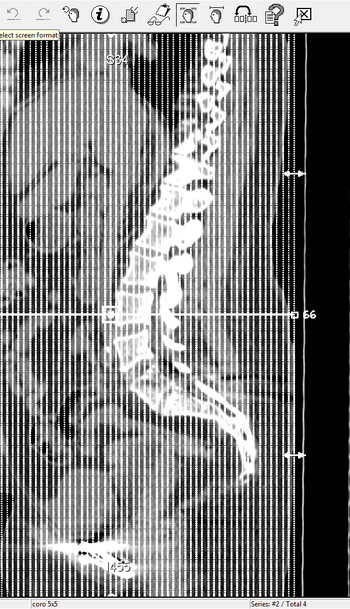

Most people don't understand why I am the way I am. I hope these x-rays give them a better idea of what I have to deal with every single day.

My spine